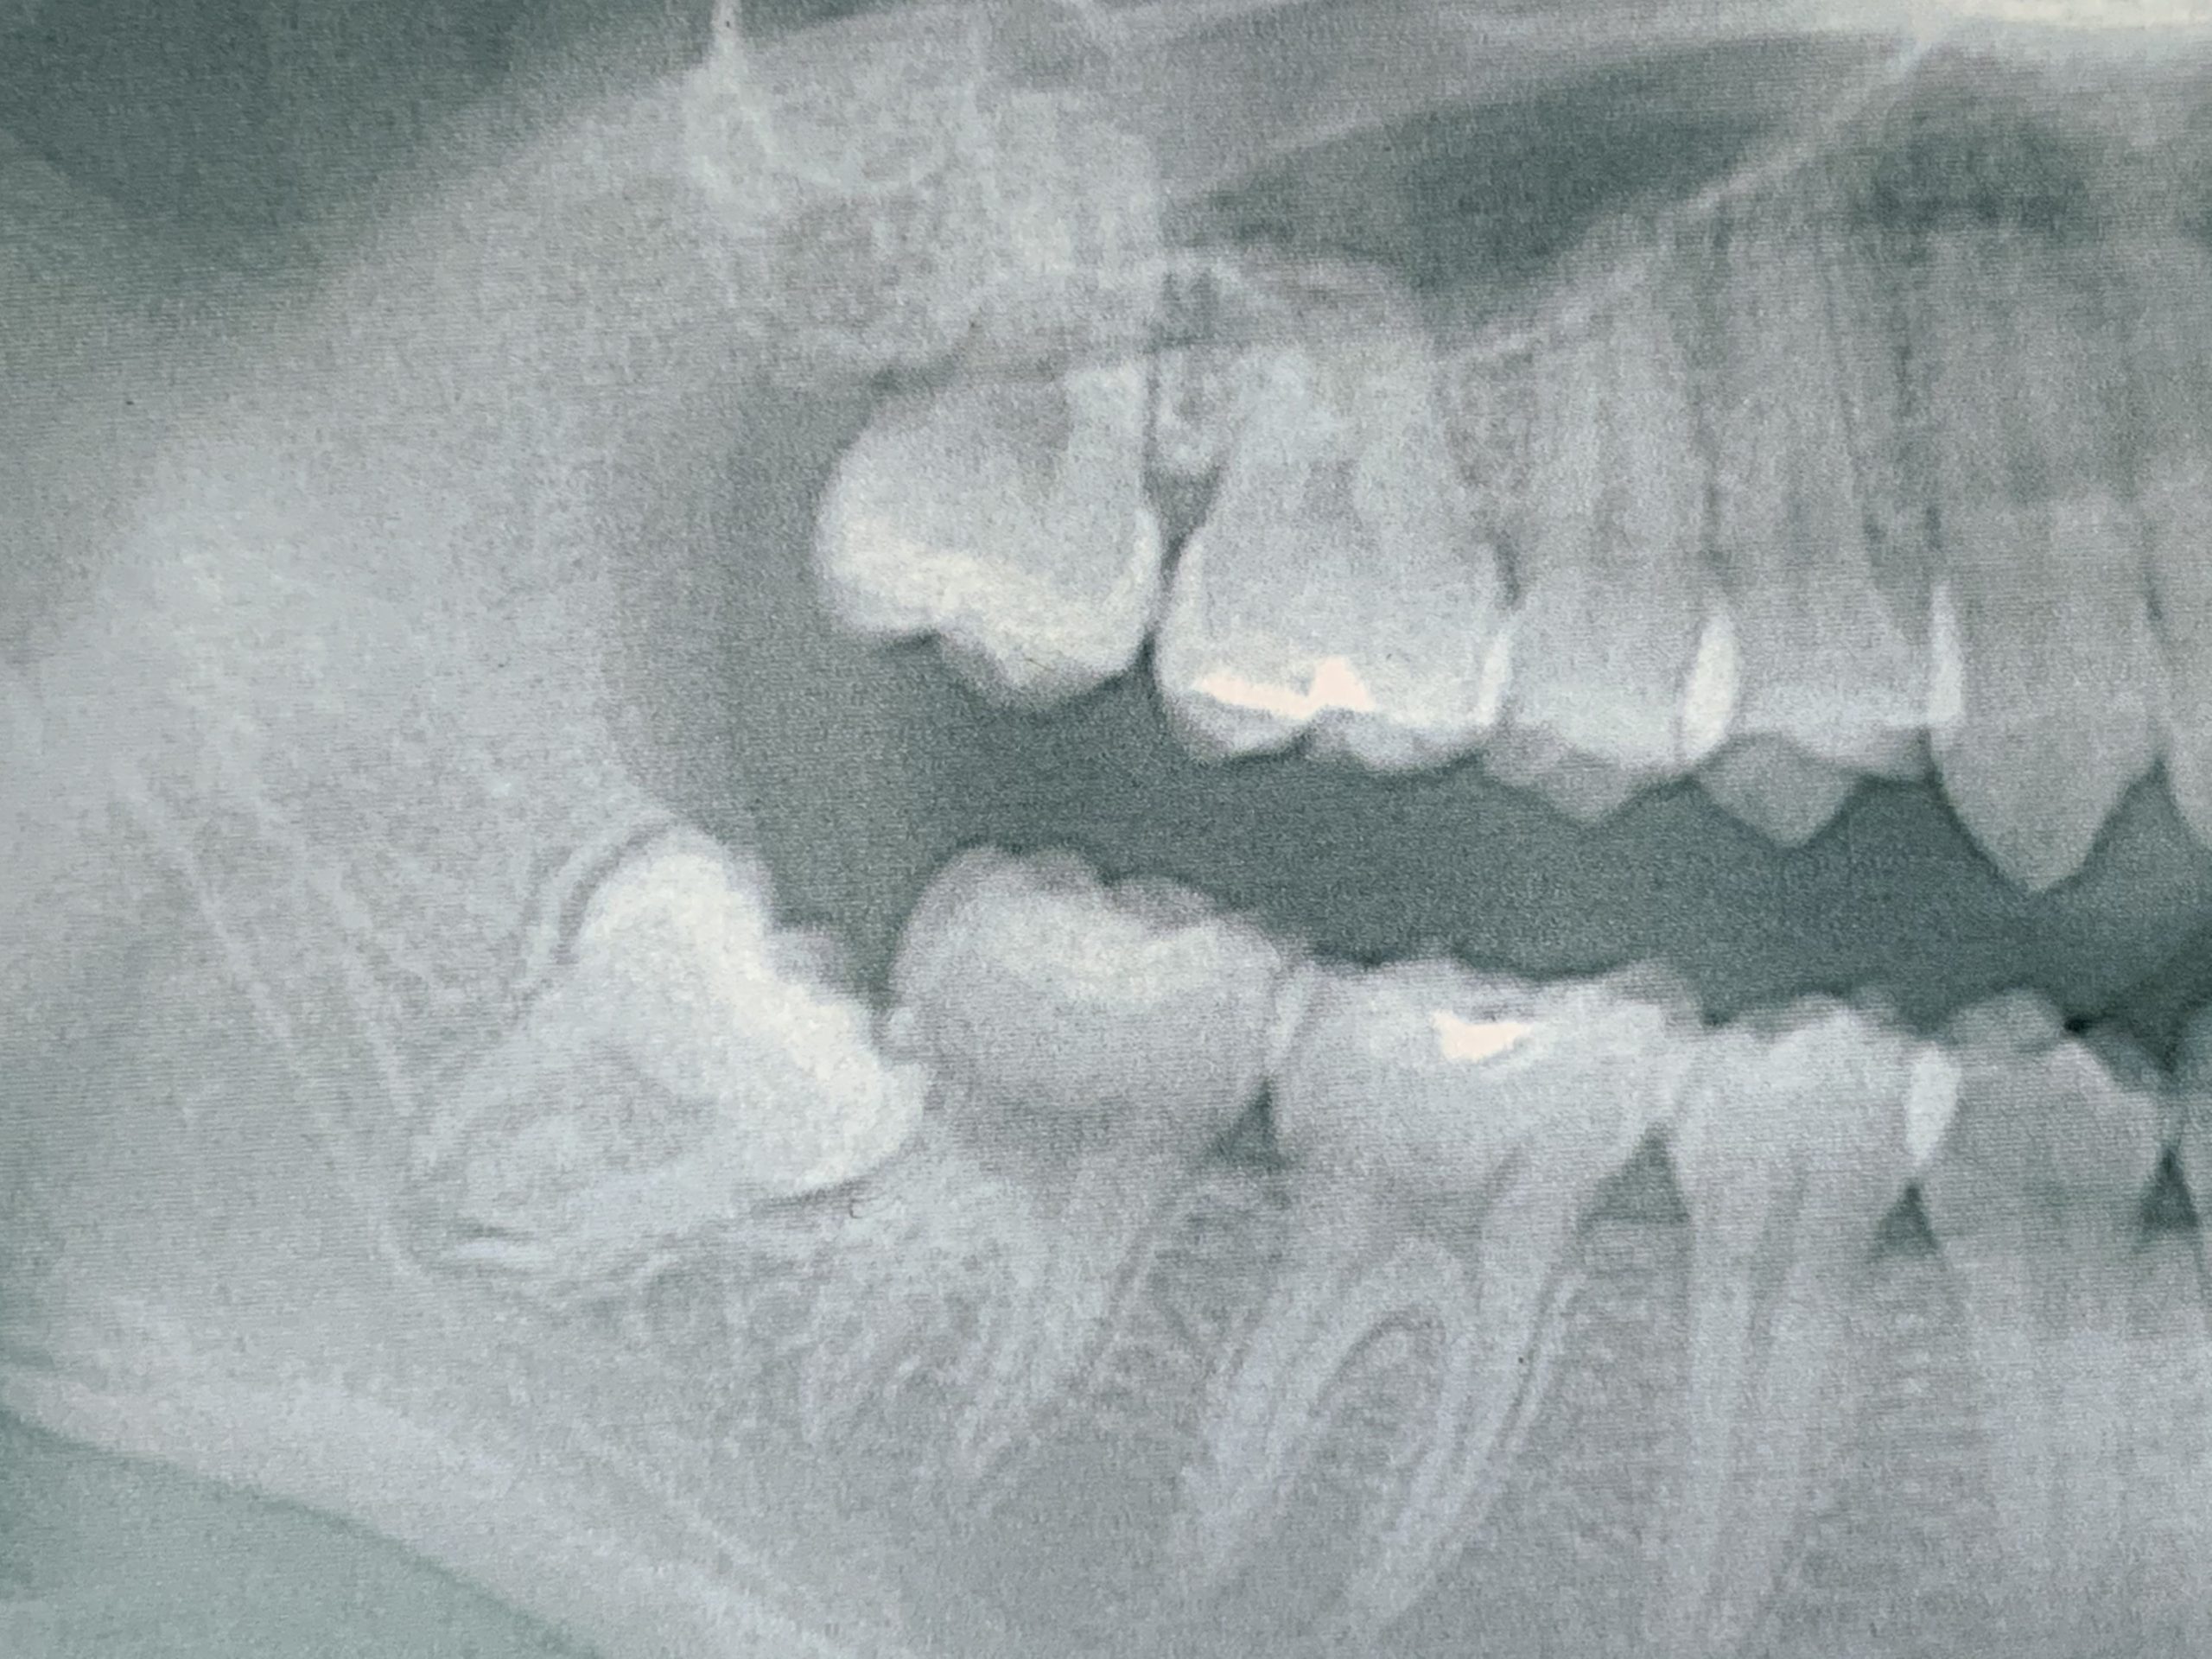

先日、親知らずを豊田厚生病院の口腔外科で抜いてきました。

抜こうと決意したのは、1ヶ月に2~3回ほど押されるような痛みが続いたからです。